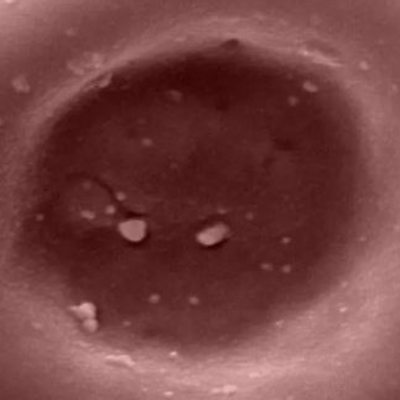

In what researchers say is a global first, blood grown in a laboratory has been put into people for the first time - albeit at this stage in just tiny amounts, a couple of spoonfuls. The aim, ultimately, is to boost the supply of vital but immensely rare blood groups, which are very difficult to get hold of. Dr Rebecca Cardigan from Cambridge University is involved in the study and she told Newshour's Tim Franks about it. (Photo shows a laboratory-grown red blood cell, which carriers oxygen and carbon dioxide around the body. Credit: NHSBT)